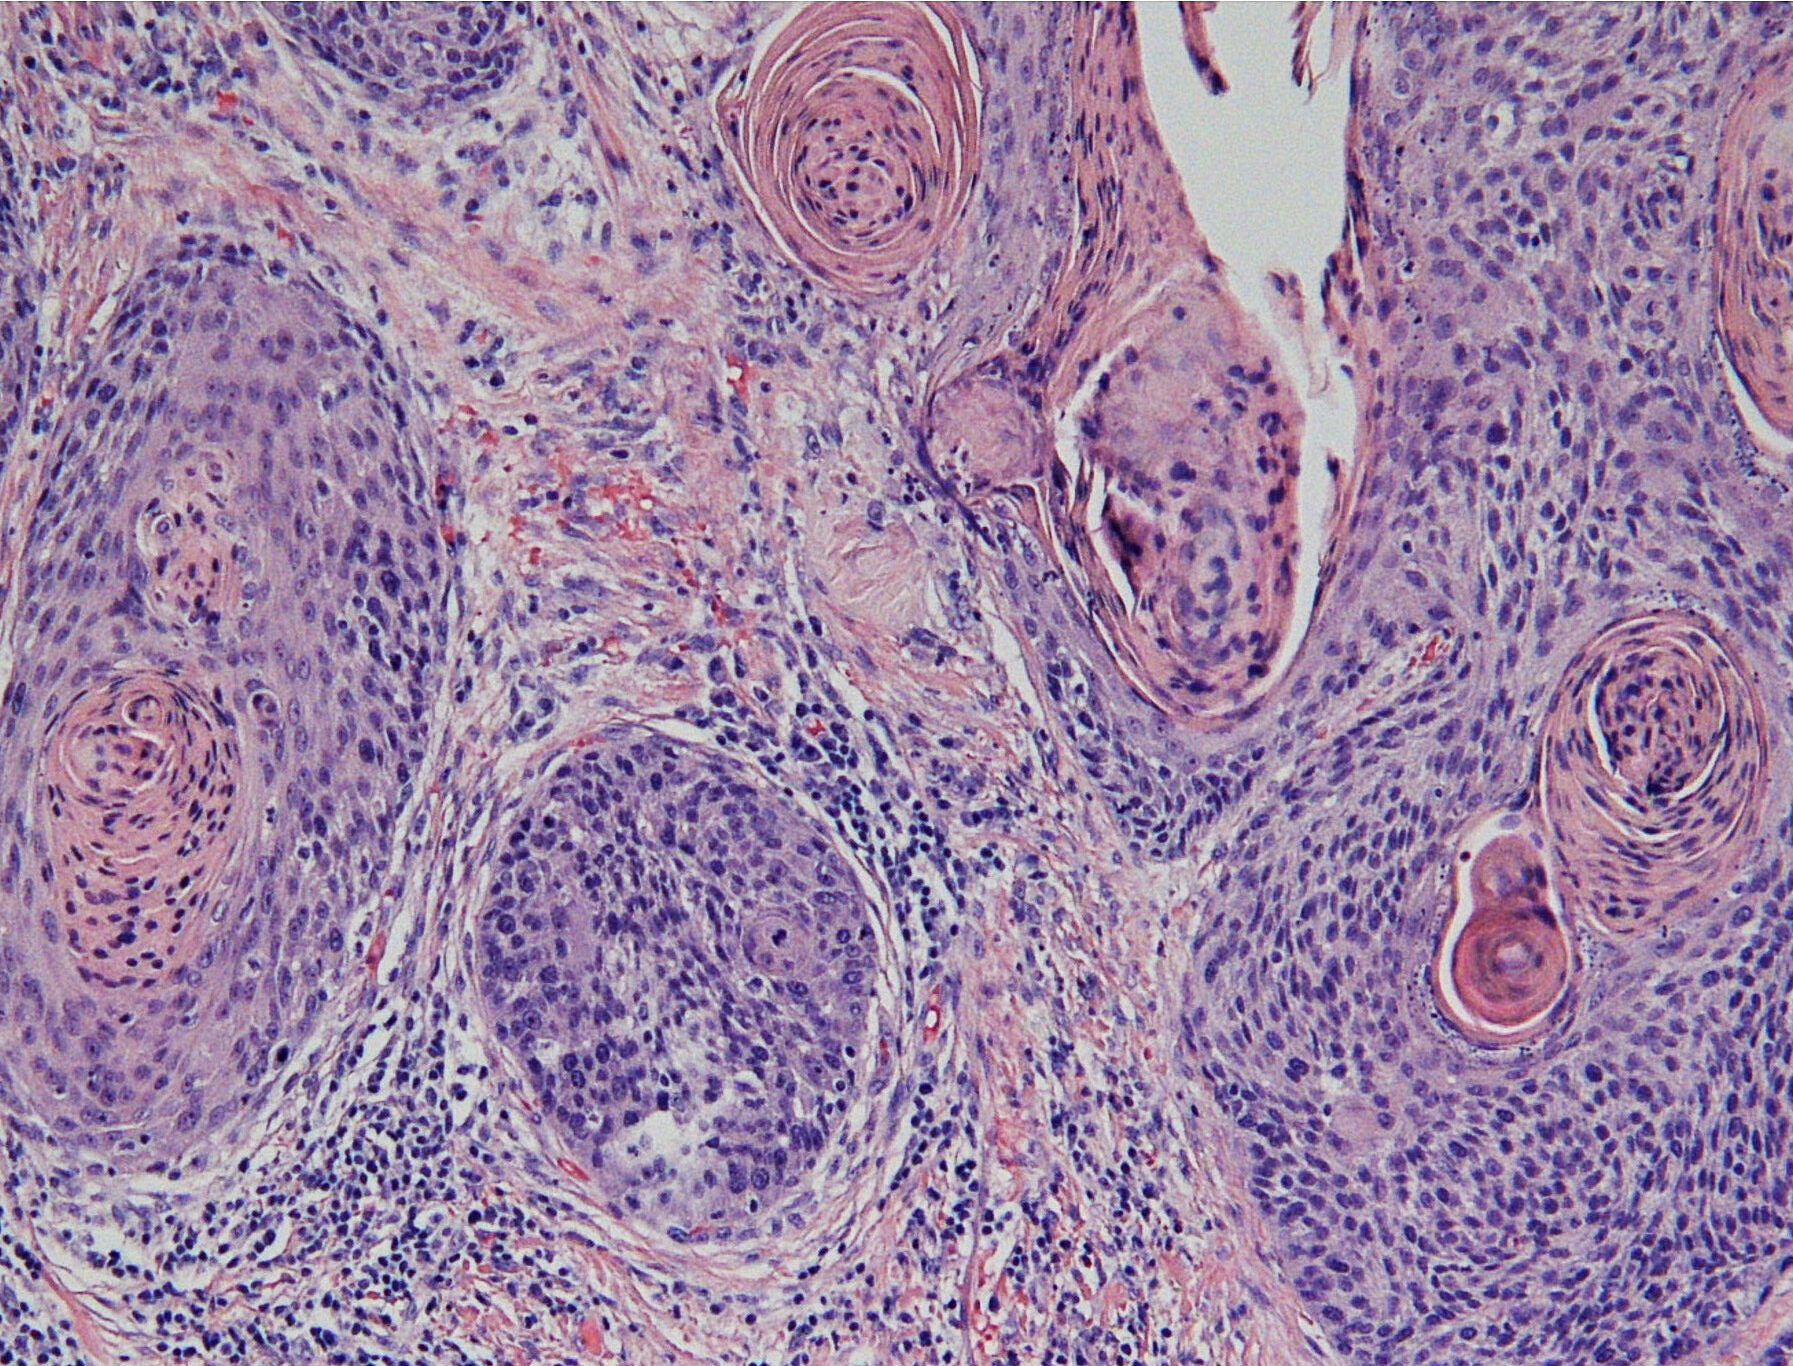

研究対象は、口腔がんの大部分を占める口腔扁平上皮癌に加え、歯原性腫瘍や唾液腺腫瘍にも広がっており、それぞれの疾患の発症機構や進展因子の解明に取り組んでいます。

口腔病理診断では、口腔顎顔面領域に発生するさまざまな疾患、特に口腔扁平上皮癌、歯原性腫瘍、唾液腺腫瘍などの診断において、高度な専門知識・経験・技術が求められます。そのため、口腔病理専門医や細胞診専門歯科医の資格取得が強く推奨されます。